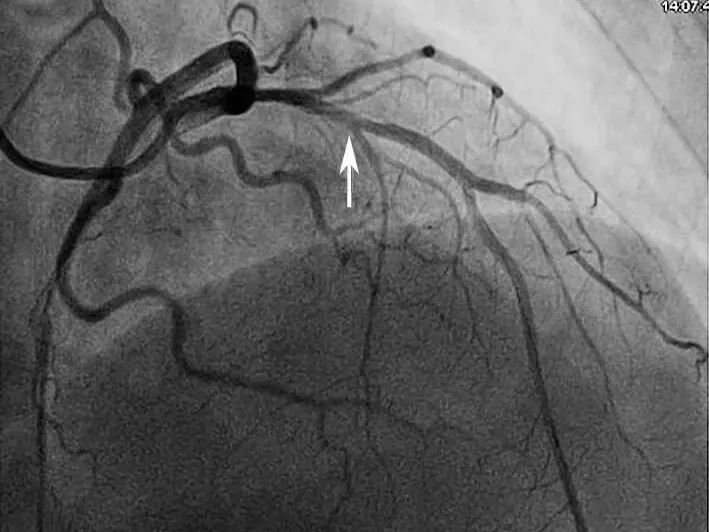

患者男性,34岁,主因胸闷憋气3周余于2015年12月22日入院。患者于2015年11月25日午餐后突然出现胸骨后憋闷、疼痛,呈压榨性,伴烦躁、大汗、恐惧,症状持续不能缓解,急诊至当地县医院,心电图提示:V2~V5导联ST段弓背向上抬高,诊断为“急性前壁心肌梗死”,给予阿司匹林300mg、氯吡格雷片600mg顿服,即刻向上级医院转诊;11月25日15点52分转入当地市医院,测血压70/40mmHg,给予多巴胺泵入,急查心肌酶升高,心电图提示:Ⅱ、Ⅲ、aVF及V2~V5导联ST段弓背向上抬高,诊断为“急性下壁、前壁心肌梗死”,于当日17时行急诊PCI手术,冠脉造影(图1)提示:左优势型,LAD开口完全闭塞,LCX粗大,远段完全闭塞,RCA未见明显狭窄,术中出现心源性休克,给予植入IABP支持,并给予LAD球囊扩张+血栓抽吸,LAD前向血流恢复TIMI 3级。术后常规抗凝、抗血小板治疗,血压稳定后给予拔除IABP(具体不详)。患者自觉症状未见好转,仍有胸闷,憋气,体力明显受限。

图1 当地心电图及急诊PCI结果

A.当地市医院急诊心电图提示:Ⅱ、Ⅲ、aVF、V2~V5导联ST段弓背向上抬高;B.急诊造影提示:LAD开口闭塞,回旋支远段栓塞;C.PCI术后,LAD TIMI 2级,LCX远段血流未恢复

图3 冠脉造影结果

A图显示前降支血流稍慢,中段可见管腔发白,怀疑血栓影;B图提示回旋支远段重度狭窄90%,血流TIMI 2级